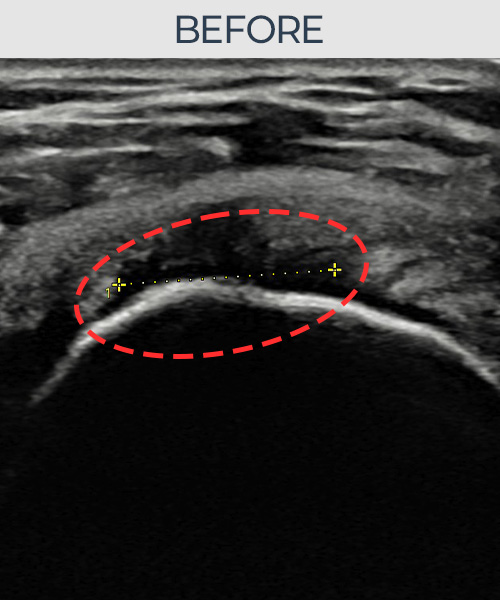

김ㅇㅇ님 · 좌측 극상근건 광범위 부분파열

좌측 어깨 광범위 파열로 수술을 권유받았으나 비수술 치료를 원해 내원하셨습니다. 초음파 검사에서 극상근건 전층에 걸친 광범위 부분파열이 확인되었으며, 어깨인대 축소봉합술 후 구조적 안정화와 기능 회복이 이루어졌습니다.